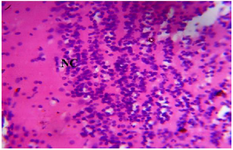

<p>Figure 7. Photomicrograph of Group One (Normal Control) section of the Dam&rsquo;s Prefrontal Cortex (x400) (H/E) shows normal active neuronal cell (NC) of the Prefrontal Cortex.</p>

Figure 7. Photomicrograph of Group One (Normal Control) section of the Dam’s Prefrontal Cortex (x400) (H/E) shows normal active neuronal cell (NC) of the Prefrontal Cortex.